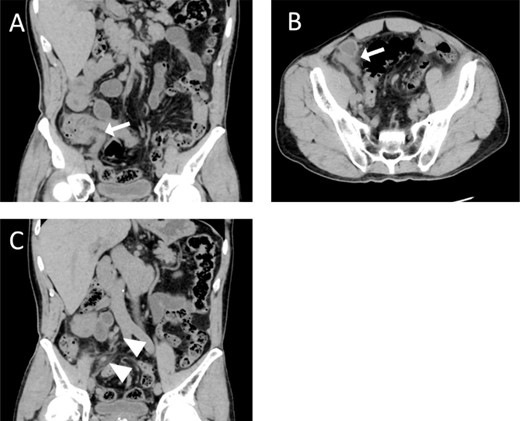

Pathological examination revealed adenocarcinoma at the surgical margin but not at the perforation site. We confirmed the intestinal tract findings seven weeks postoperatively using contrast-enhanced CT, revealing a contrast effect in the caecum and sustainably enlarged regional lymph nodes (Fig. 2A). A colonoscopy performed eight weeks postoperatively revealed advanced colon cancer in the caecum (Fig. 2B). The final diagnosis was acute appendicitis caused by caecal cancer-induced obstruction, requiring a right hemicolectomy with systematic lymphadenectomy performed nine weeks after the appendicitis surgery (Fig. 2C). The post-operative pathological diagnosis was T3N2M0, pStage IIIc (K-ras, wild type; BRAF, negative; MSI, low). Postoperative adjuvant therapy with capecitabine and oxaliplatin was initiated four weeks after the right hemicolectomy; no relapse occurred after ~10 months of chemotherapy.

Preoperative evaluation for caecal cancer. (A) Colonoscopy reveals a type 2 lesion in the caecum with a central ulcer. (B) Contrast-enhanced CT shows that the tumour area was highly stained. (C) Macro-pathological examination reveals a type 2 lesion in the cecum.